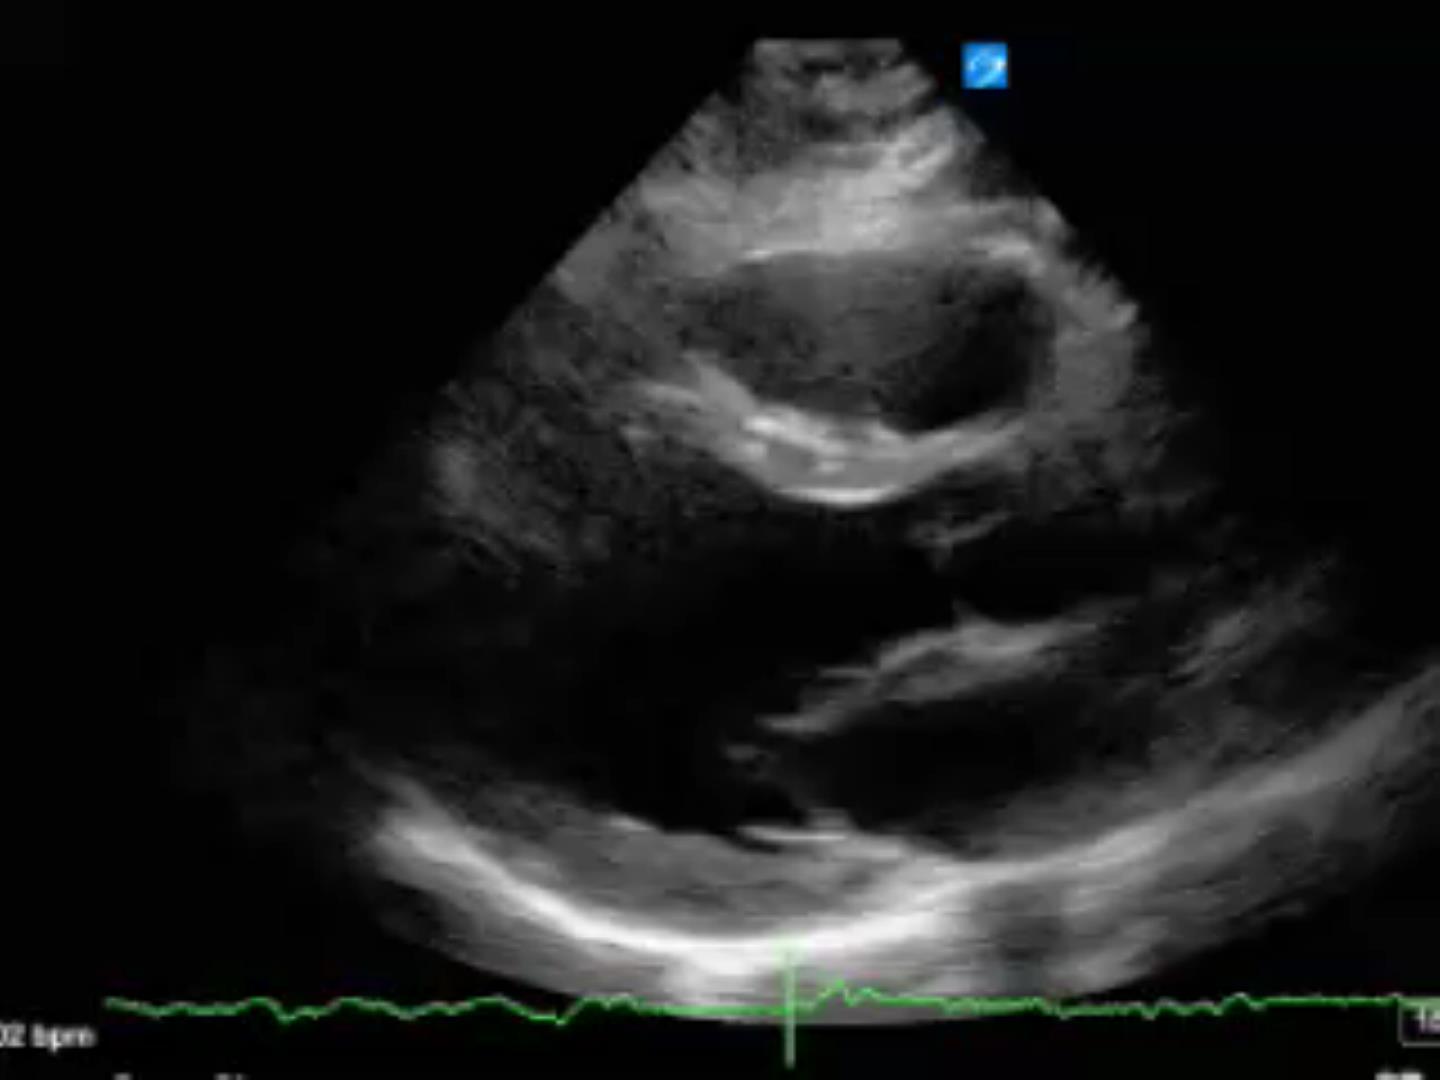

Bicuspid Aortic Valve Severe Aortic Regurgitation TransEsophageal

Bicuspid Aortic Valve Severe Aortic Regurgitation TransEsophageal Bicuspid Valve Regurgitation Others are born with connected cusps rather. Only a small portion of people have a bicuspid aortic valve. It can be years before bav causes an issue. but some people are born with an aortic valve that has two cusps, a condition called bicuspid aortic valve. a bicuspid aortic valve is a common congenital heart defect in which. Bicuspid Valve Regurgitation.